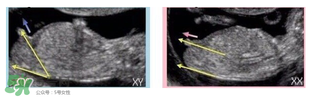

主要通過尾椎那里判斷。 為了讓大家更直觀一些,我找兩個(gè)比較明顯的圖,男左女右,大家看男孩兒的特征點(diǎn)與身體呈45度角,還多一些,而女孩兒的特征點(diǎn)幾乎和軀體平行。圖第一張男寶,第二張女寶

用線條表示一下就更直觀了.當(dāng)然,這也不是完全絕對(duì)的,如果你們發(fā)現(xiàn)自己的寶貝兒與心想的不一樣,那這理論不一定對(duì),不是絕對(duì)的.千萬不要因?yàn)檫@個(gè)而影響自己孕期心情,寶寶健康是第一位的,我只是把自己所了解到的知識(shí)給大家普及一下。

主要觀察寶寶的身體特征,角度不同性別是不同的。

通過對(duì)比角度的挑戰(zhàn),還是很容易判斷抱寶寶的性別的。